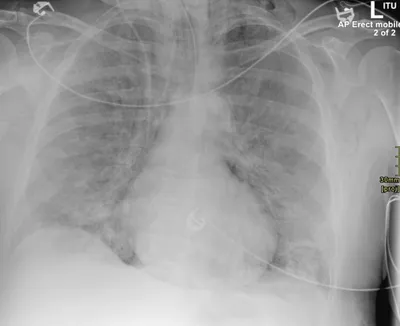

Pneumomediastinum Radiology Images

This collection contains 1 radiology images related to pneumomediastinum, including various imaging modalities such as X-rays, MRIs, CT scans, and ultrasound images commonly used in medical diagnosis and education.